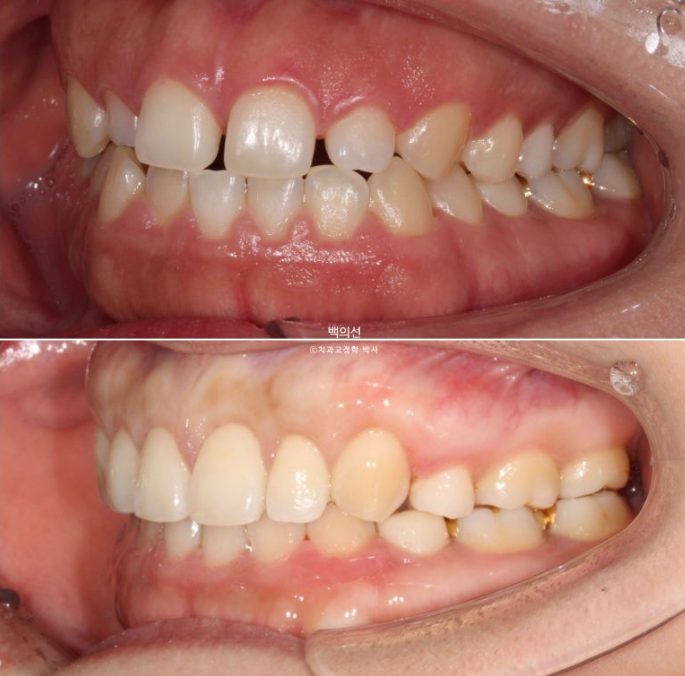

웃을 때 잇몸이 많이 보이는 거미스마일이 눈에 띕니다.

돌출에 의해 입술이 편하게 안다물러지는 입술부전증 그리고 이로인한 호두턱 (호두주름)도 보입니다.

실제로 골격 분석을 해보면 무턱이 심하지는 않지만, 돌출입으로 인한 턱끝 과긴장 즉 호두턱은 없는 무턱도 만들어내는 주범입니다.

발치공간 폐쇄, 앞니 후방이동, 거미스마일 해소와 하관길이 및 무턱의 해소를 위한 전체치열 함입을 진행합니다.

어금니 교합은 물샐틈 없이 좋습니다.

어금니 교합관계는 좌우 모두 1급 입니다.

턱끝의 비대칭은 그대로이지만 턱끝 긴장이 풀리면서 턱라인이 한결 개선이 되었습니다.

특히 하관의 길이가 짧아진 것도 눈에 띕니다.

하관 길이의 변화는 후반 엑스레이 중첩에서 다시 보여드리겠습니다.

아름다운 치아비율과 스마일라인이 돋보입니다.

왜소치 쪽으로 돌아가 있던 앞니 중심선은 이제 코, 인중과 맞아졌네요.

거미스마일의 확실한 개선

23.07~25.07

자연스럽고 예쁜 입매가 돋보입니다.

돌출로 입이 잘 안물려서 생긴 호두주름 때문에 무턱의 오명을 썼던 예쁜 턱라인이 비로소 드러났습니다.